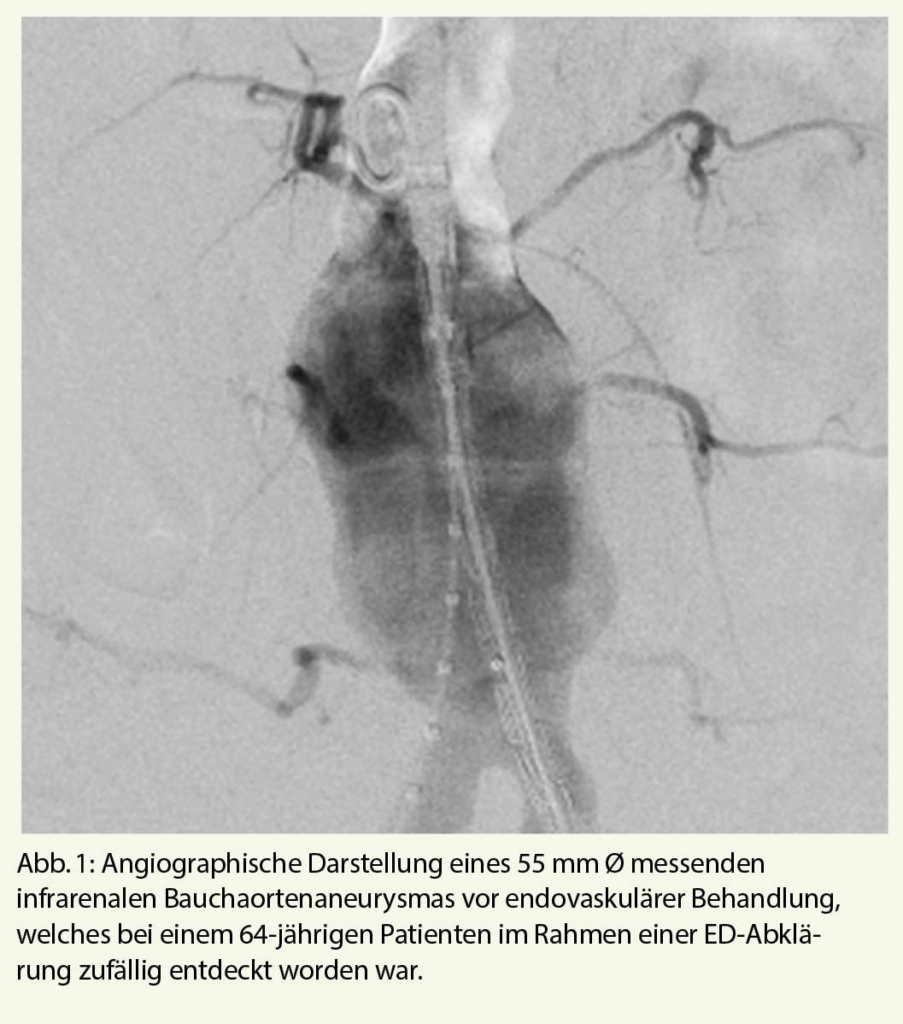

Sobald die Diagnose einer arteriell bedingten ED gesichert ist, empfiehlt sich ein fachärztliches Workup. Häufig finden sich bei Patienten mit arteriell bedingter ED auch Pathologien in anderen arteriellen Stromgebieten (Abb. 1, 2).

Insgesamt zeigten in dieser Arbeit 168/200 (84,0%) männliche Patienten mehrere zufällige CT-Befunde. Andere häufige Zufallsbefunde sind Aneurysma, Tumore, Prostata-Hyperplasien, Steatosis hepatis, Kolon-Divertikulose, Hernien, Nieren- und Leberzysten und Degeneration des Spinalkanals (5).